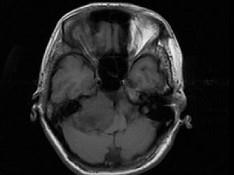

女,45岁,右耳听力下降半年余,CT检查如图,最可能诊断为 ( )

• A.脑膜瘤

• B.继发性胆脂瘤

• C.三叉神经瘤

• D.原发性胆脂瘤

• E.听神经瘤

答案: E